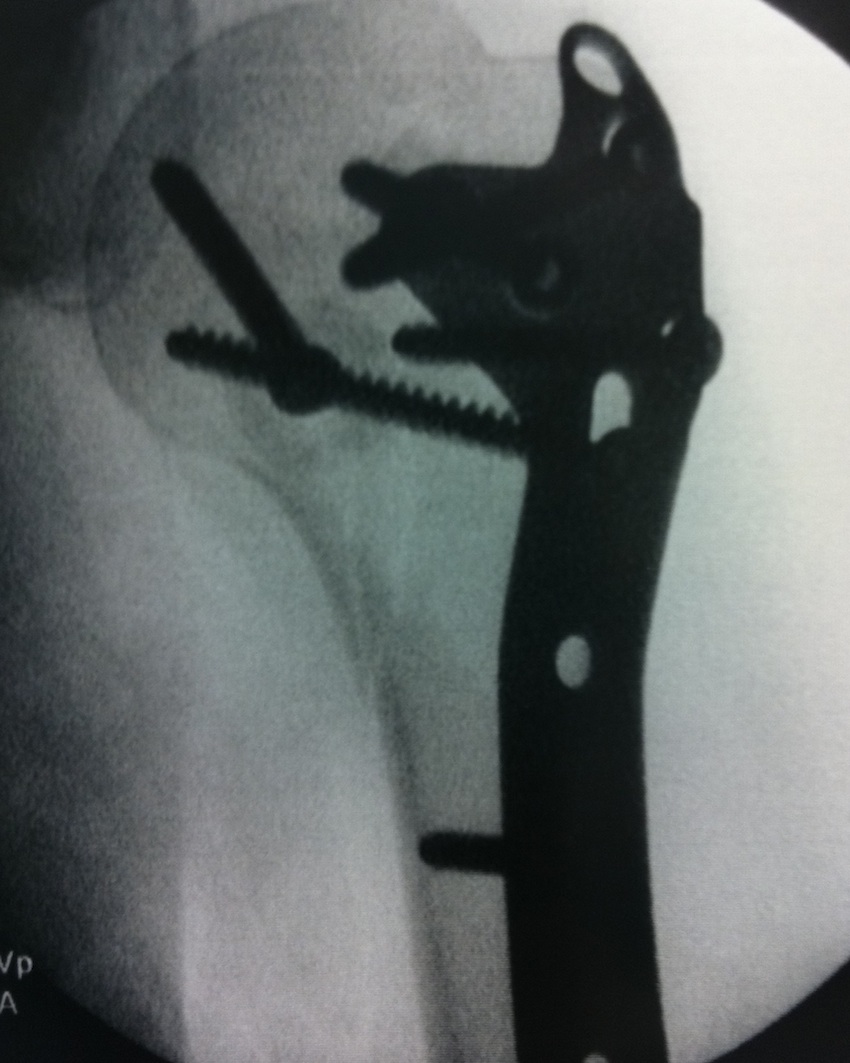

proximal humerus fracture Background ORIF with locking plate Arthroplasty Greater tuberosity fractures Lesser tuberosity fractures / avulsions Book traversal links for Proximal humerus fractures ‹ Pectoralis Major Tears Up Background ›